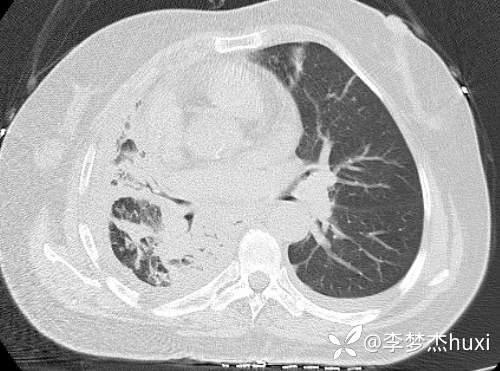

8.17胸部CT: